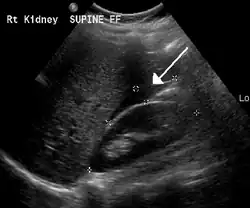

An ultrasound showing a gestational sac with the fetal heart in the fallopian tube has a very high specificity for ectopic pregnancy. It involves a long, thin transducer, covered with the conducting gel and a plastic/latex sheath and inserted into the vagina.[38] Transvaginal ultrasonography has a sensitivity of at least 90% for ectopic pregnancy.[5] The diagnostic ultrasonographic finding in ectopic pregnancy is an adnexal mass that moves separately from the ovary. In around 60% of cases, it is an inhomogeneous or a noncystic adnexal mass, sometimes known as the "blob sign". It is generally spherical, but a more tubular appearance may be seen in the case of hematosalpinx. This sign has been estimated to have a sensitivity of 84% and a specificity of 99% in diagnosing ectopic pregnancy.[5] In the study estimating these values, the blob sign had a positive predictive value of 96% and a negative predictive value of 95%.[5] The visualization of an empty extrauterine gestational sac is sometimes known as the "bagel sign", and is present in around 20% of cases.[5] In another 20% of cases, there is visualization of a gestational sac containing a yolk sac or an embryo.[5] Ectopic pregnancies where there is visualization of cardiac activity are sometimes termed "viable ectopic".[5]

-

Transvaginal ultrasonography of an ectopic pregnancy, showing the field of view in the following image -

A "blob sign", which consists of the ectopic pregnancy. The ovary is distinguished from it by having follicles, whereof one is visible in the field. This patient had an intrauterine device (IUD) with progestogen, whose cross-section is visible in the field, leaving an ultrasound shadow distally to it. -

Ultrasound image showing an ectopic pregnancy where a gestational sac and fetus have been formed

A small amount of anechogenic-free fluid in the recto-uterine pouch is commonly found in both intrauterine and ectopic pregnancies.[5] The presence of echogenic fluid is estimated at between 28 and 56% of women with an ectopic pregnancy, and strongly indicates the presence of hemoperitoneum.[5] However, it does not necessarily result from tubal rupture but is commonly a result from leakage from the distal tubal opening.[5] As a rule of thumb, the finding of free fluid is significant if it reaches the fundus or is present in the vesico-uterine pouch.[5] A further marker of serious intra-abdominal bleeding is the presence of fluid in the hepatorenal recess of the subhepatic space.[5]